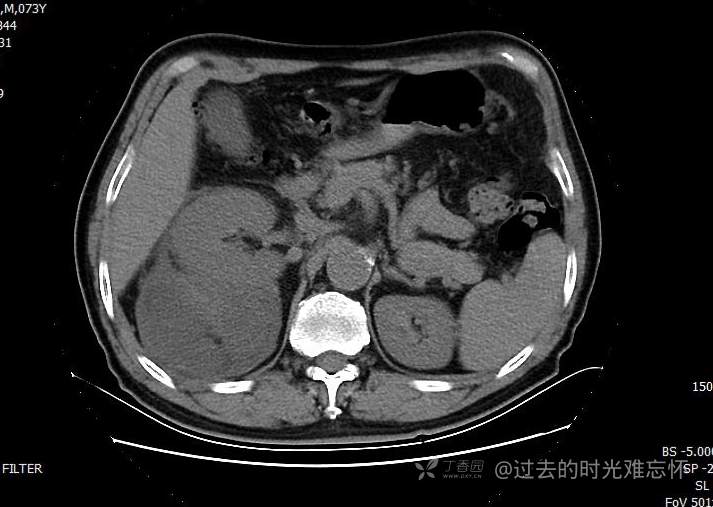

患者性别:男

患者年龄:73岁

主诉:咳嗽1月余。曾有血尿一次。后背部酸痛不适1-2年左右,无明显消瘦。

辅助检查:CT MRI

临床诊断:占位

治疗经过:手术